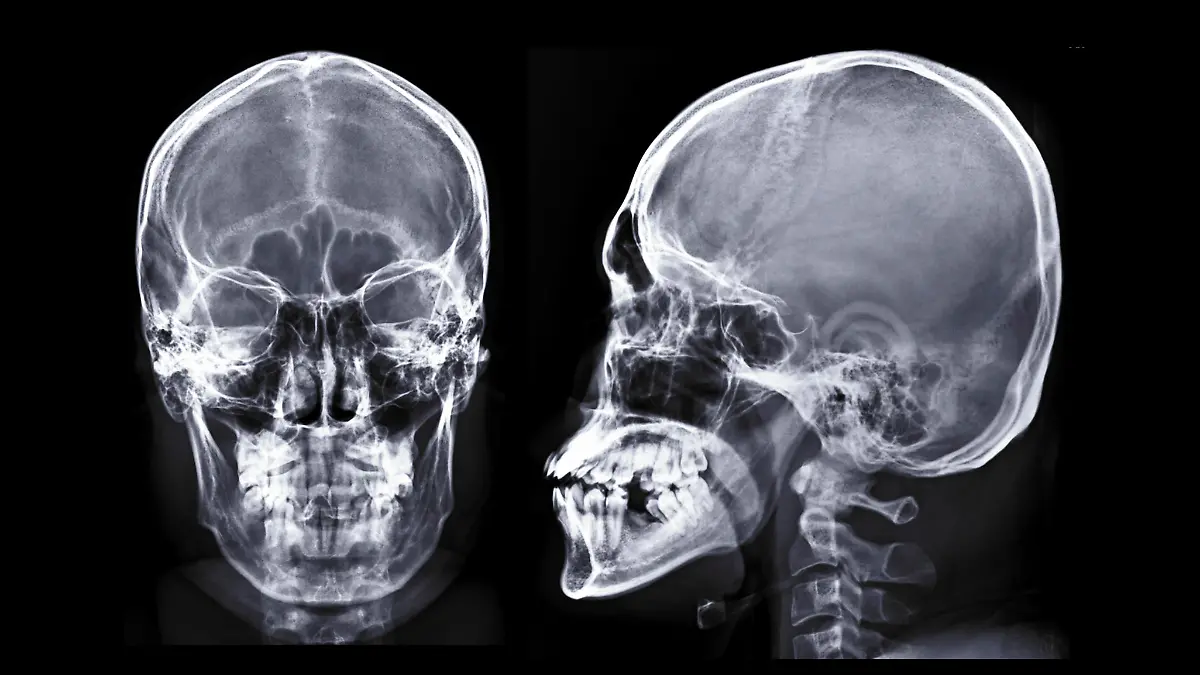

Der Schädel ist als Knochengebilde ein Bestandteil des Skeletts. Er ist grob in zwei Bereiche zu unterteilen: Der Hirnschädel, die stabile Bedeckung um das Hirn herum, besteht aus sieben fest miteinander verbundenen einzelnen Knochenplatten, die durchschnittlich rund 6 Millimeter dick sind. Nach vorne hin zeigt sich der Gesichtsschädel. Seine charakteristische Form mit den vielen Wölbungen und Kanten ist die Grundlage des menschlichen Gesichts. Er besteht aus ungefähr 15 einzelnen kleinen Knochen, wobei manche noch das Zungenbein und die Knochen des Gehörganges dazu zählen. Nach unten hin an den Schädel angeschlossen ist das Kiefergelenk.

Die wichtigste Aufgabe des Schädels besteht im Schutz des Gehirns. Da das Hirn von zentraler Bedeutung für das Überleben ist, bettet der Schädel die weiche Gehirnmasse sicher in seinem Inneren ein. Aus diesem Grund ist das Schädeldach besonders stabil und dick. Es ist wohl kein Zufall, dass die weiteren wichtigen Sinnesorgane (Mund, Augen, Nase, Ohren) ebenfalls alle im Schädel angelegt sind: Er bietet größtmöglichen Schutz. Dabei zeigt sich, dass die knöcherne Konstruktion schlau aufgebaut ist. Um Gewicht einzusparen und den Schädel proportional nicht unnötig schwer zu machen, sind gerade die vorderen Bereiche des Gesichtsschädels überwiegend in Form von leichten aber stabilen Nebenhöhlen konstruiert.